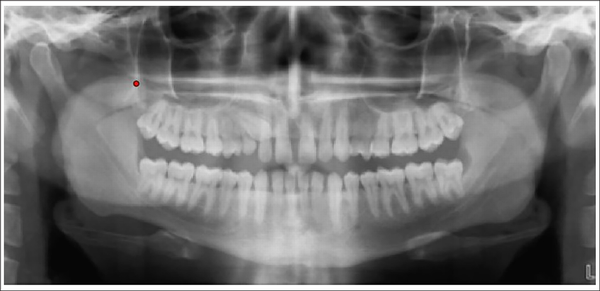

Step 1: The OPGs were uploaded in JPEG/TIFF format and cropped using a bounding box of uniform size of 80 × 215 pixels (Figures 2 and 3).

Point for Cropping Orthopantomogram.

Cropped Image of Orthopantomogram.